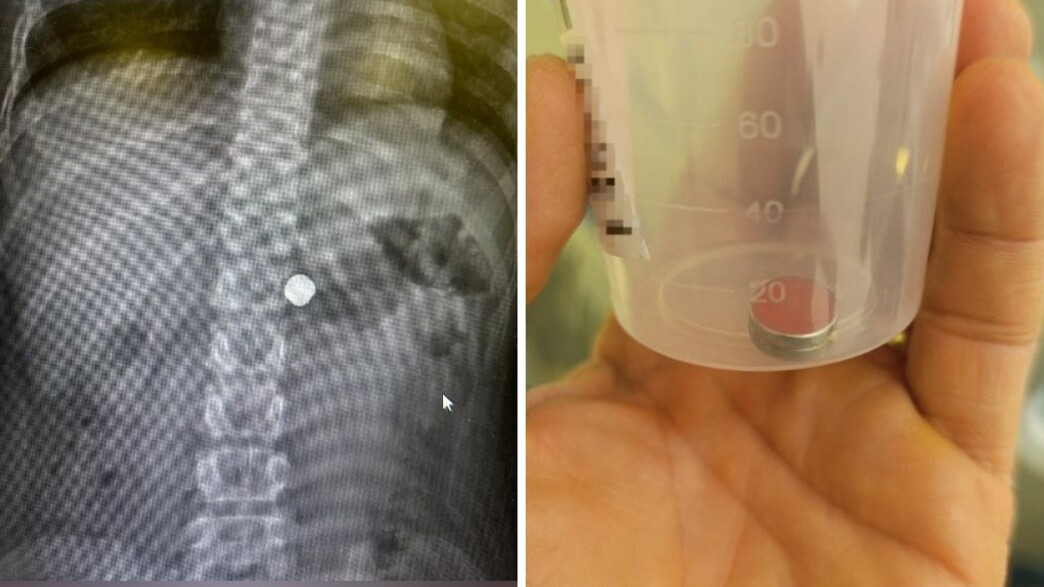

האב שמע את הילדה בת ה-10 צועקת "בלעתי מגנט"

בת העשר דיווחה לאביה כי בלעה שני מגנטים, ולאחר שהתייעץ עם הצ'אט הבין כי מדובר במצב המחייב ייעוץ רפואי. הוא שוחח עם רופא ובעקבות המלצתו, מיהר עם הילדה למרכז הרפואי מאיר, לאחר שבלעה שני מגנטים במהלך משחק